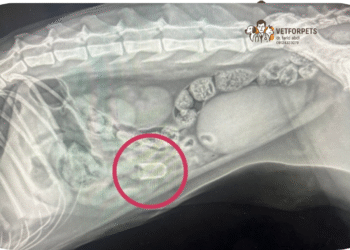

خوردن اجسام خارجی توسط حیوانات خانگی